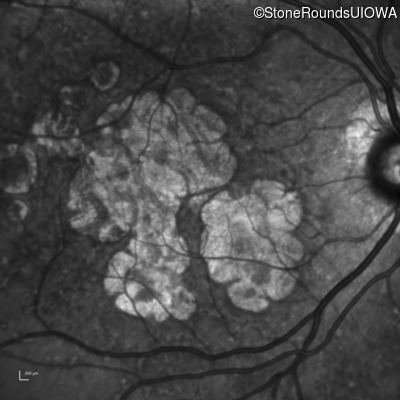

Blue Autofluorescence - Right - 20/25

Exemplar

Blue Autofluorescence - Left - 20/32 -2